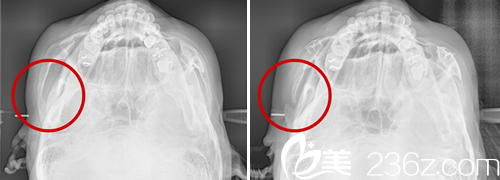

在術(shù)中,鄭院長會現(xiàn)在前顴骨做L型切口,其次從耳朵上方鬢角位置做一厘米小切口,切開側(cè)顴骨部分并進(jìn)行回旋固定,來達(dá)到改善顴骨。

以鄭院長豐富的手術(shù)經(jīng)驗(yàn)為基礎(chǔ),可以在求美者口腔內(nèi)做小切口進(jìn)行手術(shù),不但可以在減少手術(shù)創(chuàng)傷的前提下對顴骨突出部位進(jìn)行改善,還能降低顴骨術(shù)后面部皮膚下垂情況的發(fā)生,使面部輪廓更加協(xié)調(diào)柔和。